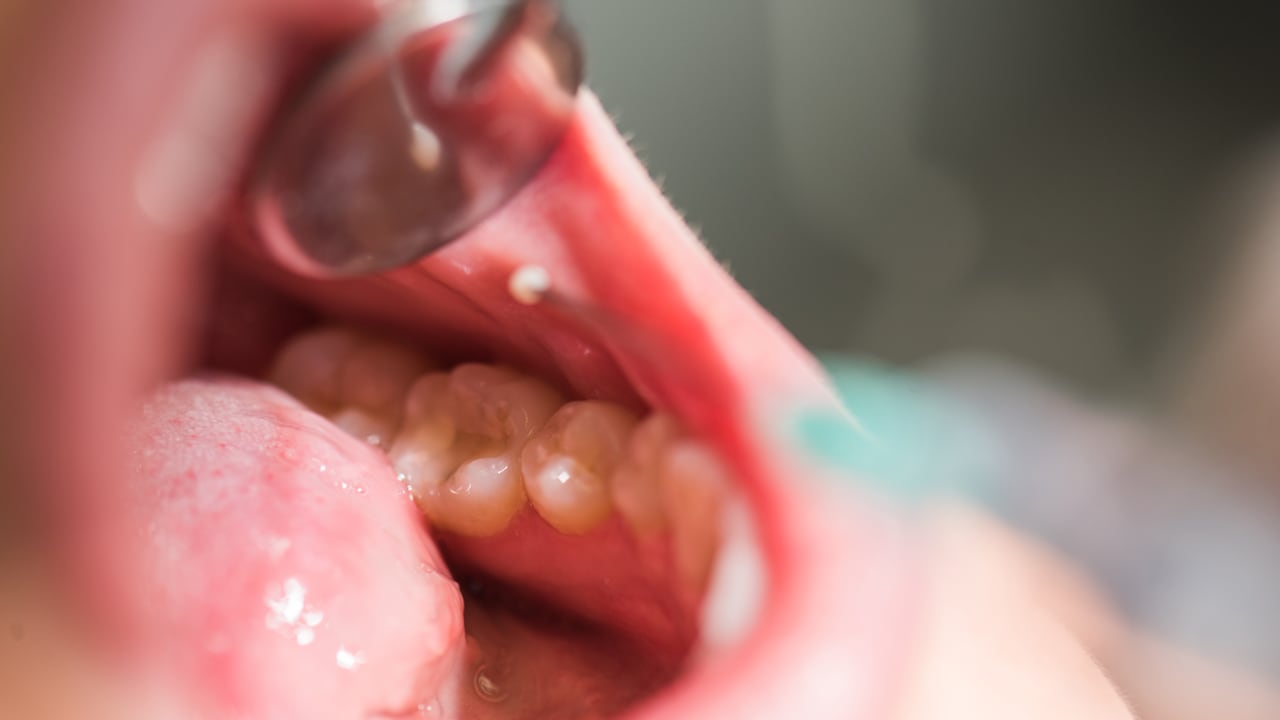

Al momento que estas aparecen, primero se observan una serie de manchas de color blanco alrededor de los dientes, las cuales se van oscureciendo a medida que se agrava la condición. Las caries se esconden en la superficie entre los dientes y es difícil de percibirlas a simple vista, lo cual implica que para conocer a cabalidad el estado de la infección, se necesita una radiografía intraoral para ser diagnosticada.

SEPA distingue que hay tres tipos de caries:

- Caries coronales: son las más frecuentes, especialmente se presentan en niños, niñas y adultos jóvenes. En este caso, la afectación ocurre en las partes de los dientes encargadas de la masticación.